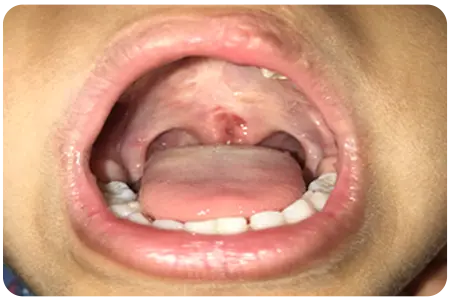

Nasoendoscopy is a minimally invasive procedure that allows our specialists to closely examine the velum, lateral pharyngeal wall and posterior pharyngeal wall using a thin, flexible scope.

This detailed view helps us accurately assess and diagnose speech and resonance issues, ensuring precise and effective treatment plans. Experience expert care and state-of-the-art diagnostics with our nasoendoscopy services at VPD Clinic.